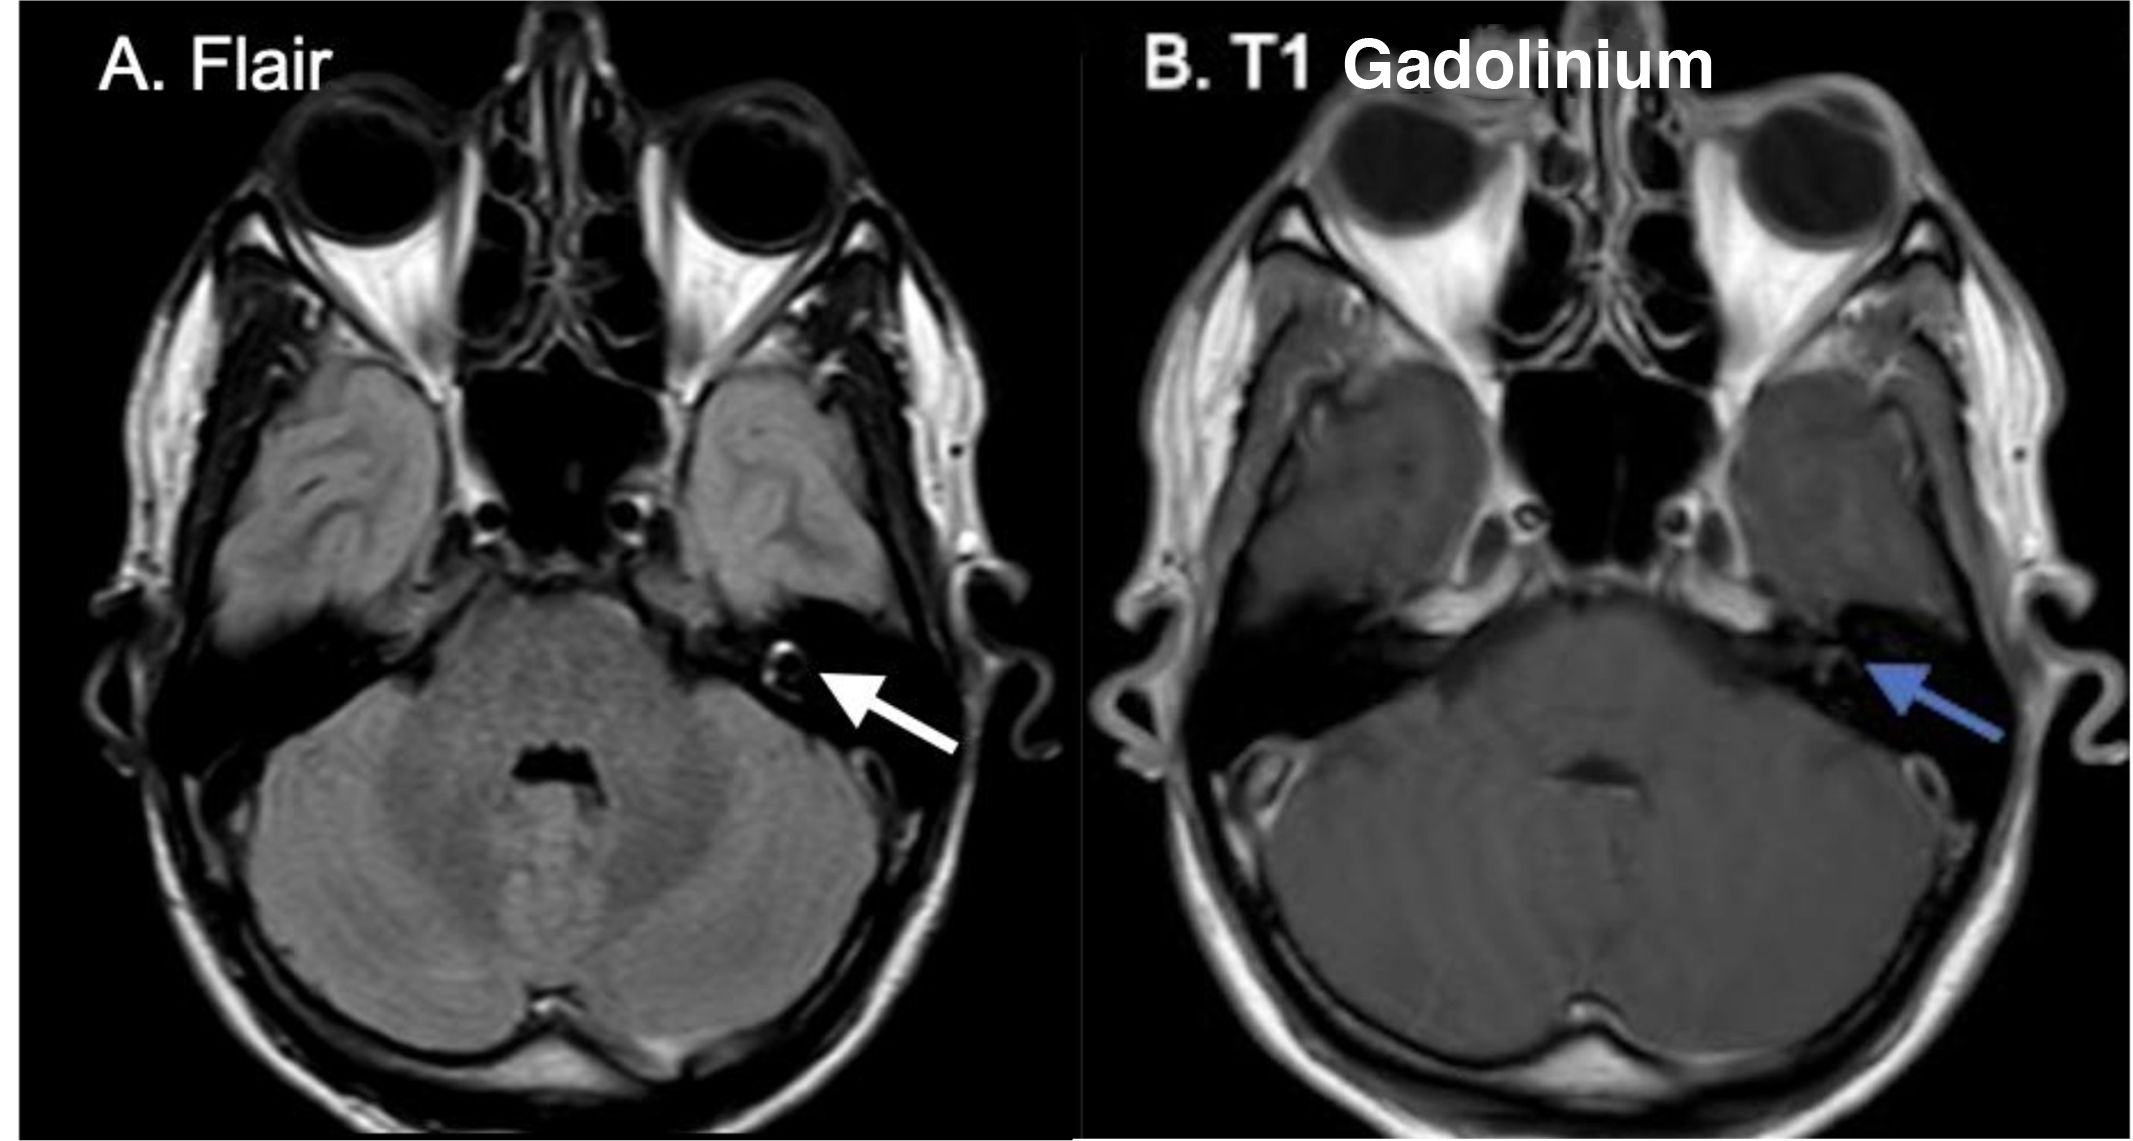

Medicina Clínica (English Edition) Sudden hearing loss and vertigo following physical exercise

Sudden hearing loss and vertigo following physical exercise

Hipoacusia súbita y vértigo tras ejercicio físico